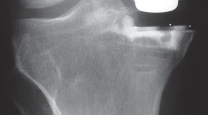

التصوير الطبي ضروري لتأكيد التشخيص وتحديد مدى تلف المفصل:

-

الأشعة السينية العادية (Plain Radiographs):

- المنظر الأمامي الخلفي (AP): يُظهر الركبة من الأمام.

- المنظر الجانبي (Lateral): يُظهر الركبة من الجانب.

- المنظر الخلفي الأمامي المثني (PA Flexed): يسمح بتقييم أفضل للجزء الخلفي من الركبة وقد يكشف عن تغيرات أكبر في الحجرة الخلفية الوحشية.

- منظر شروق الشمس (Sunrise/Patellofemoral): لتقييم المفصل الرضفي الفخذي.

- الأشعة السينية الطويلة للطرف السفلي بالكامل (Full-length standing radiographs): من الورك إلى الكاحل، وهي مفيدة جدًا، خاصة إذا تم استخدام تقنيات الملاحة الحاسوبية. تُظهر هذه الأشعة المحاذاة الكلية للطرف السفلي.